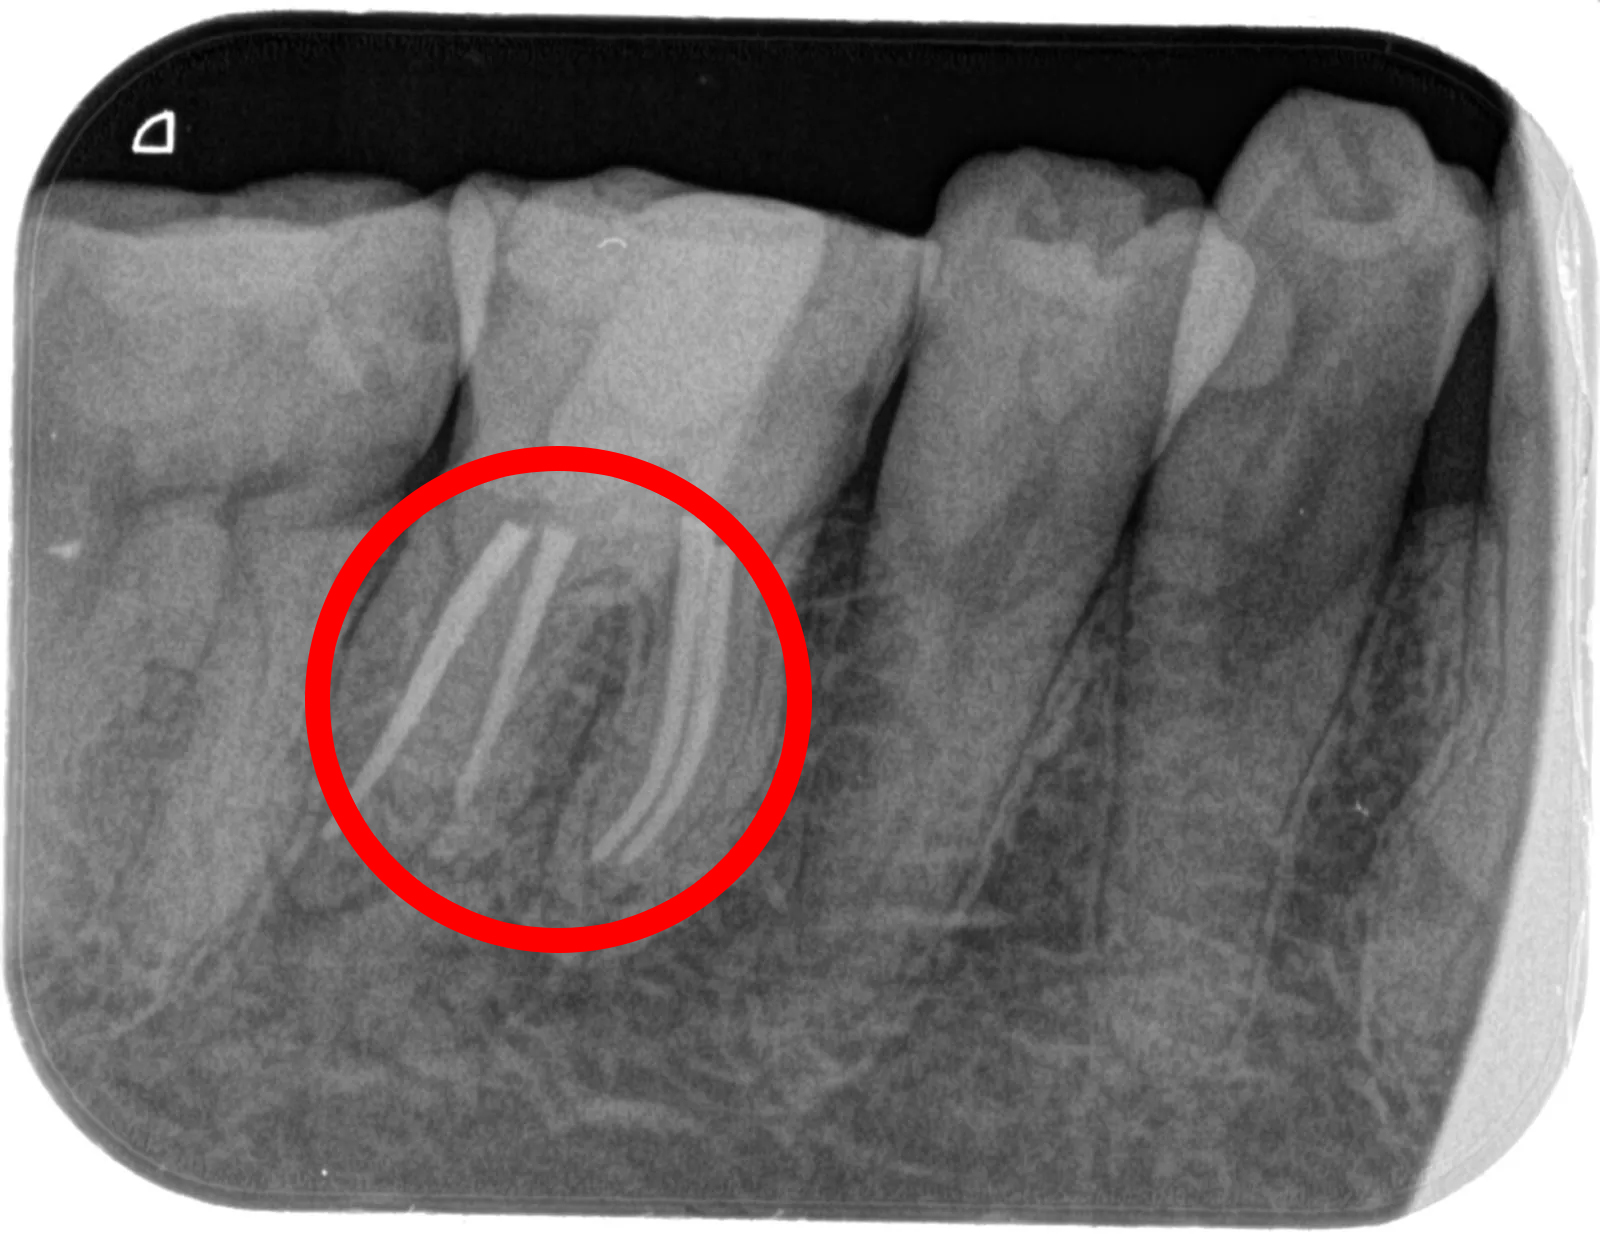

• 治療前

• 治療後

■主訴:右下の奥歯が冷たいものでしみる、何もしなくてもズキズキする

■詳細:当院の歯内治療専門医による根管治療(抜髄)、NiTiファイル用いて根管を拡大形成、根管洗浄したのちにバイオセラミックシーラー(MTA系)を用いて根管充填、支台築造

■治療期間:治療開始から二回の来院で処置終了。間は一週間あける。一回の治療は約一時間半程度

■治療費:14.3万円 (上部構造は別)

■治療のリスク:一般の保険医による治療に比べるとはるかに可能性は低いが、歯が薄くなるので破折のリスクが上がる